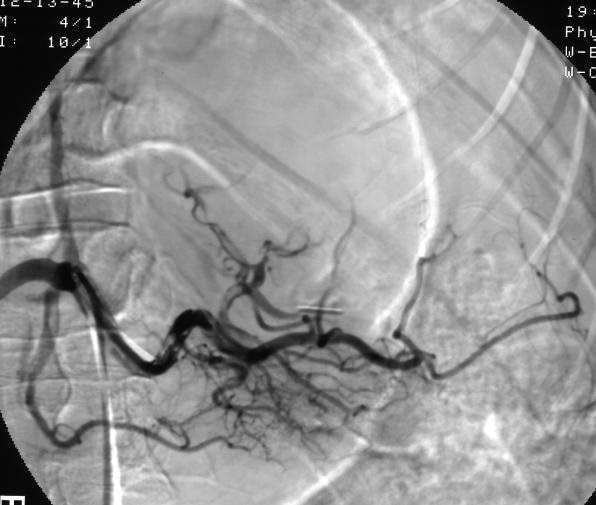

(2)超选择远端栓塞

钝性脾外伤主要关注是非手术处理,介入和脾拯救,而不是开腹探查和脾切除。理想化治疗和减少开腹手术,适合非手术治疗脾外伤病人的发现是非常重要的;发现血管损伤和活动性出血可考虑进行血管栓塞。脾外伤栓塞后脾拯救率77~97%。 尽管脾动脉栓塞技术精确的适应症还有争论,但是CT评估和临床特征应该可以发现持续出血的病人。近端脾动脉栓塞和远端超选择脾动脉分支的栓塞脾拯救和栓塞后并发症的结果相似。一旦有可能弹簧栓子释放到胰大动脉开口以远的脾动脉【11~14】。